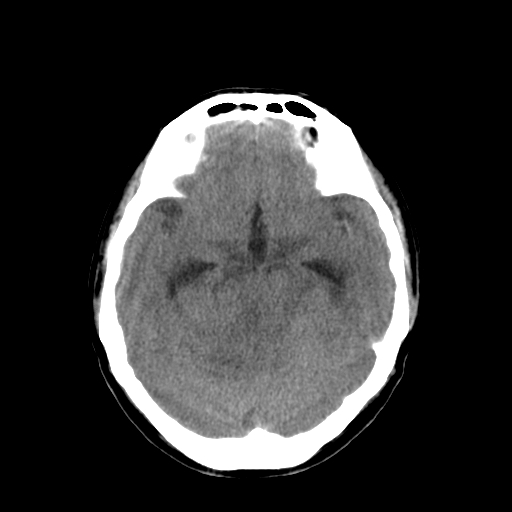

男,34岁,头痛数天。请大家看看是否有占位.

右侧小脑半球占位压迫四脑室并幕上脑积水征像;建议增强或mr检查

右侧小脑半球病变压迫四脑室并幂上积水征象,考虑占位.

右侧小脑半球占位压迫四脑室并幕上脑积水征像;建议增强或mr检查 。支持!

梗阻性脑积水,间质性脑肿胀,幕下占位可能,必须进一步检查。